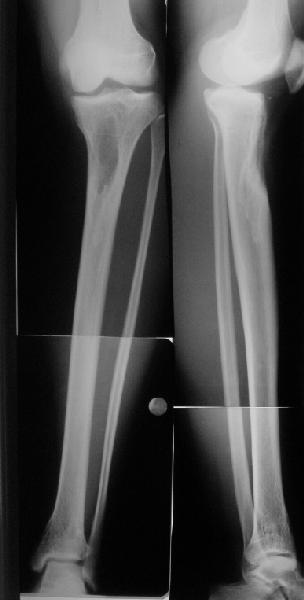

Продолжение обсуждения, начатого в октябре прошлого года (см. здесь) Наконец-то оперировали эту пациентку. Биопсию сделали - опухолевого ничего нет. Пока все участвовавшие в обследовании смежные специалисты и ортопеды сошлись, что это молокальная монооссальная фиброзная дисплазия. 20 марта наложили аппарат, сделали чрескожную остеотомию. К 3 апреля все докрутили. Сегодня заштифтовали. Начальные и итоговые снимки в приложении. Рекурвацию можно было еще немного больше устранить, и чуть кзади сместить диафиз. Но вроде и так ничего выглядит, по сравнению с тем, что было. Комментарии приветствуются.

ничего не понимаю в детской и ортопедии, но в боковой проекции нет рекурвации,

а даже немного гиперкоррекция, что по-моему есть хорошо. Кортикалы по задней стенке совпадают, диафиз на одну неправду кзади.